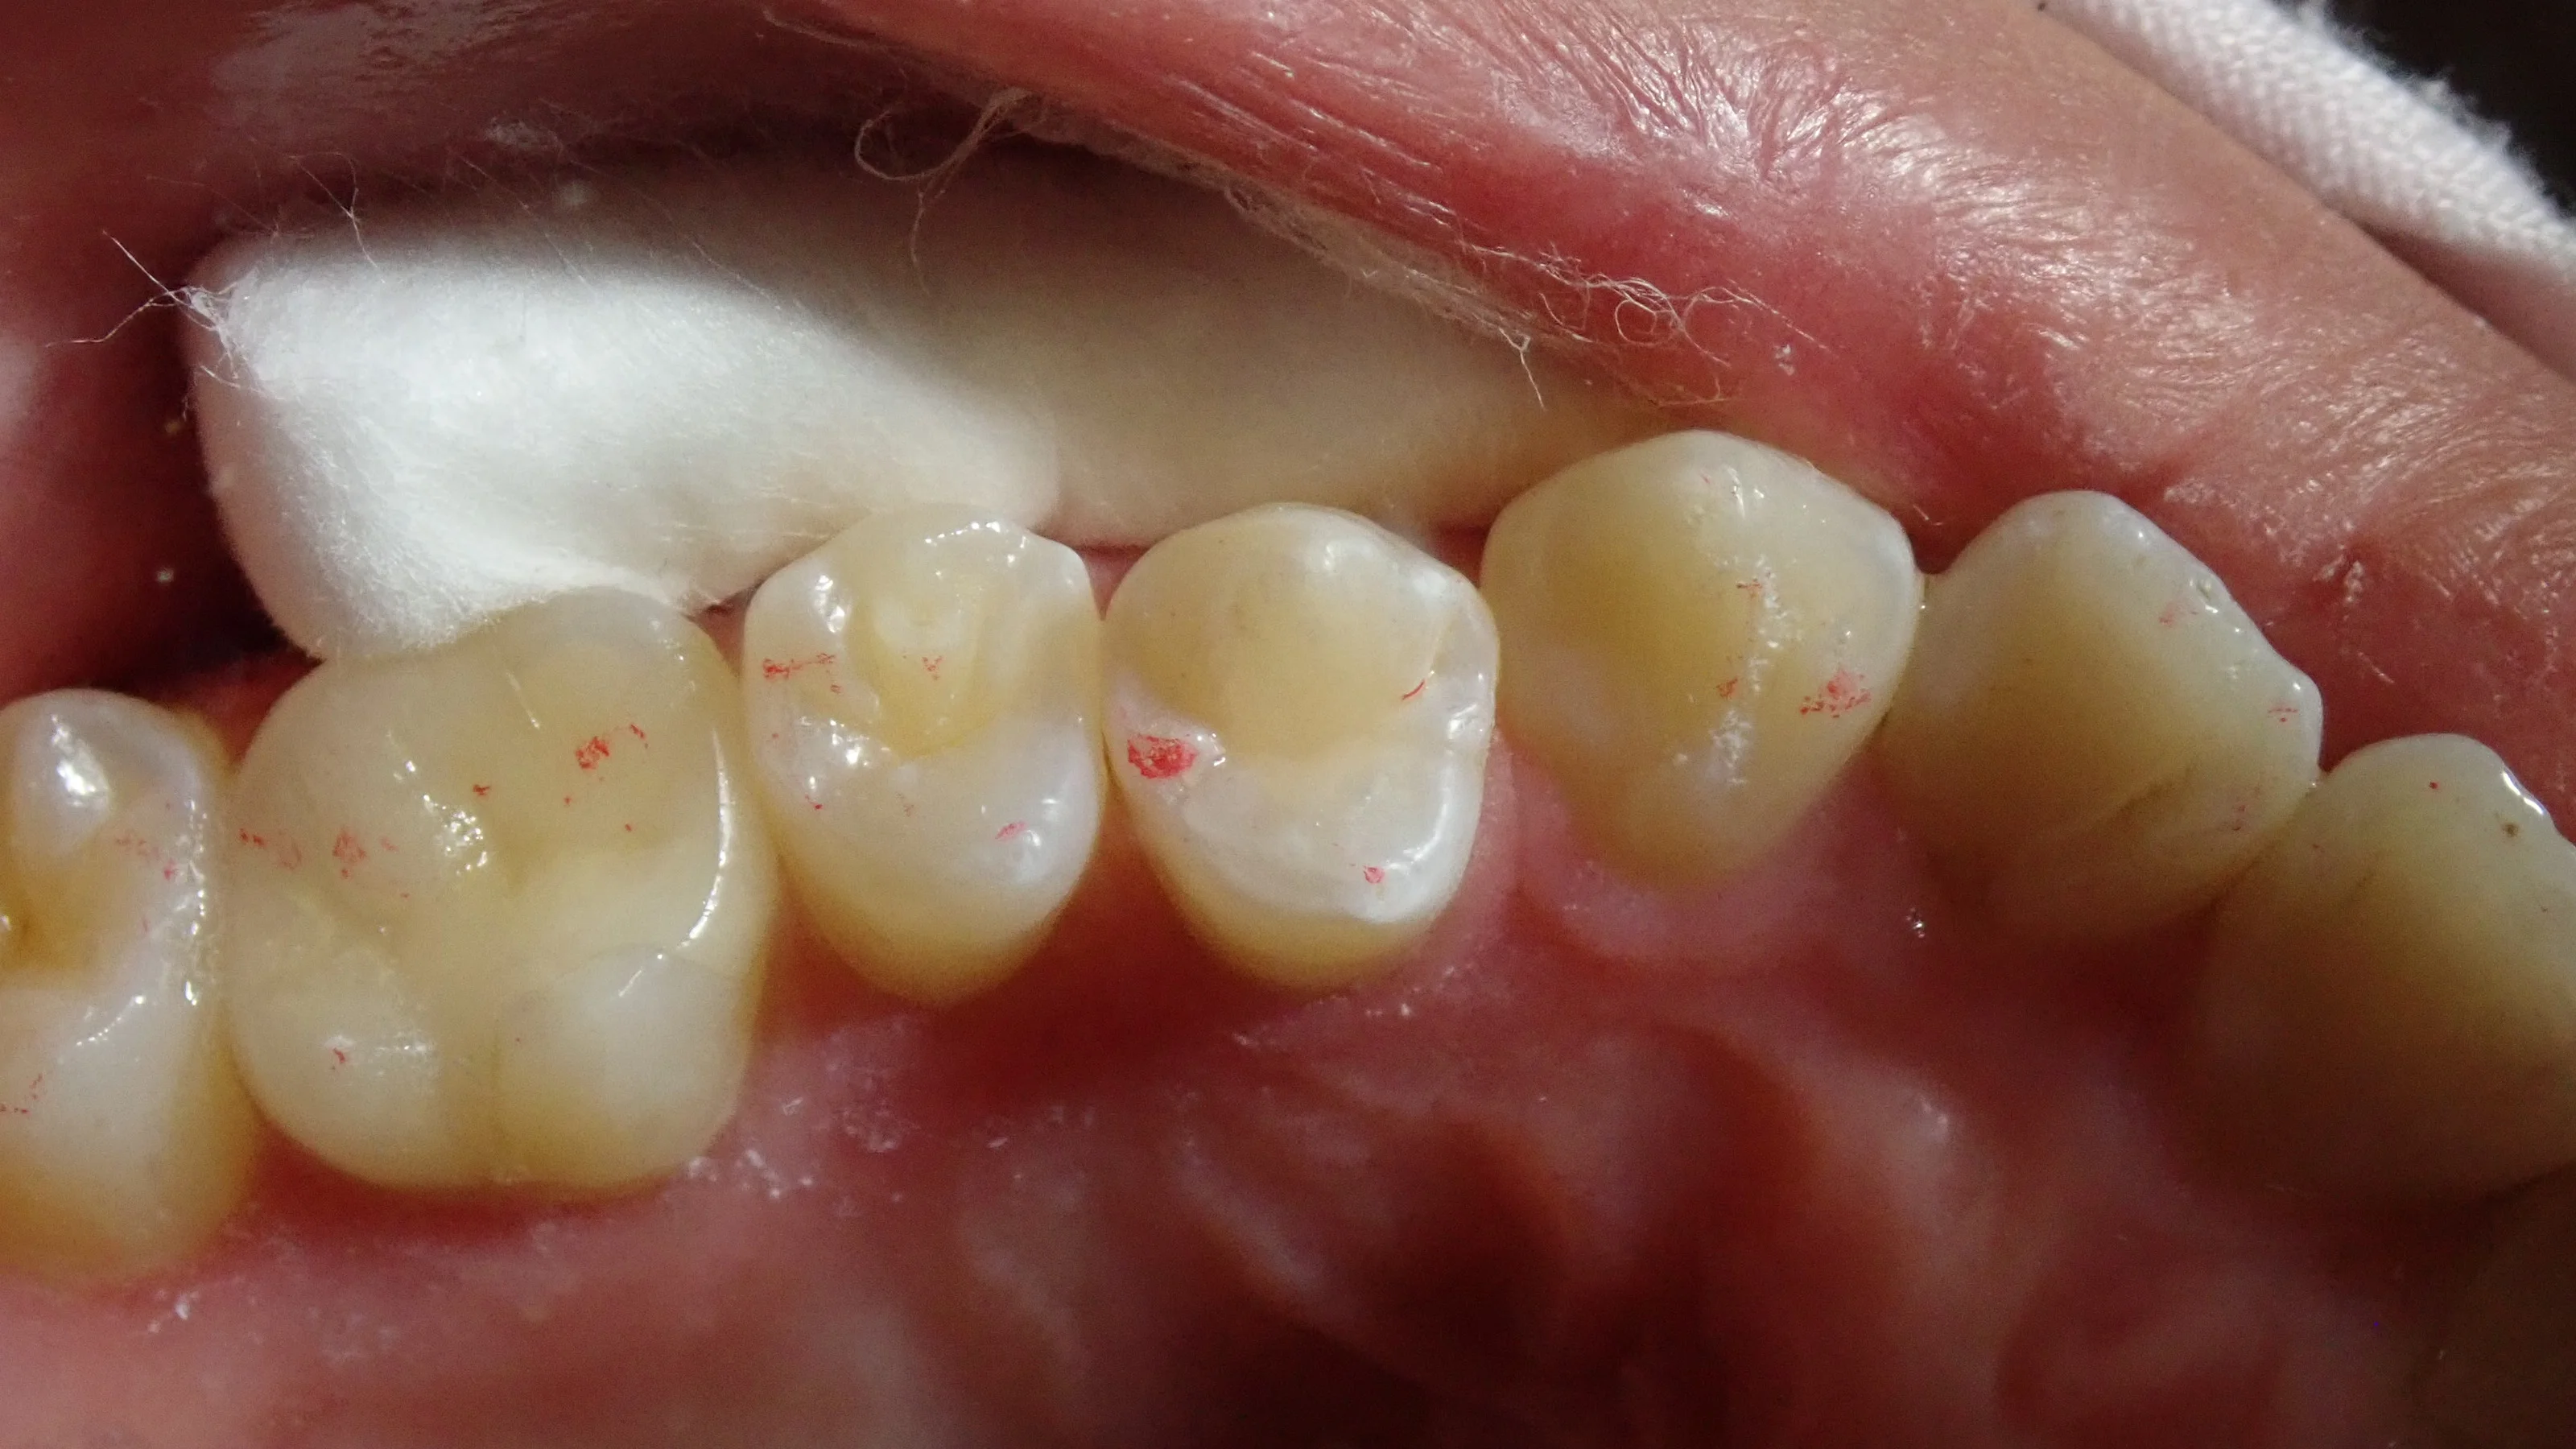

そして、最終的に詰め終わったのがこちら。

色の違いによる段差は少なからず出てしまっていますが、それでも、被せ物などを入れるよりは歯を削る量としても最小で済ませられます。

何度もこのブログでもお伝えしていますが、歯の治療とはチケット制みたいなものです。

20枚綴りのチケットがあったとして、治療の毎に数枚を消費していきます。

こんな感じで、小さく詰めた場合はチケットとしては1枚~2枚で済みますが、被せ物となると一気に5~10枚消費するような感じになります。